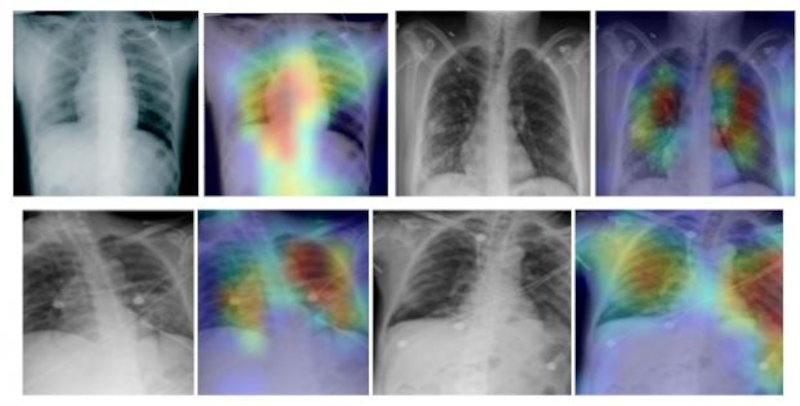

Τεχνολογία ακτίνων Χ χρησιμοποιείται για τη σύγκριση ακτινογραφιών των υπόπτων φορέων του κορωνοϊού με μια βάση δεδομένων περίπου 3.000 ακτινογραφιών από ασθενείς της Covid-19, υγιή άτομα και ασθενείς που πάσχουν από ιογενείς πνευμονίες.

Στη συνέχεια το πρόγραμμα τεχνητής νοημοσύνης χρησιμοποιεί έναν αλγόριθμο για να συγκρίνει απεικονιστικές εξετάσεις και να κάνει τη διάγνωση. Η τεχνική αυτή, σύμφωνα με δημοσίευμα της Daily Mail, διαπιστώθηκε ότι είναι ακριβής σε ποσοστό 98%.